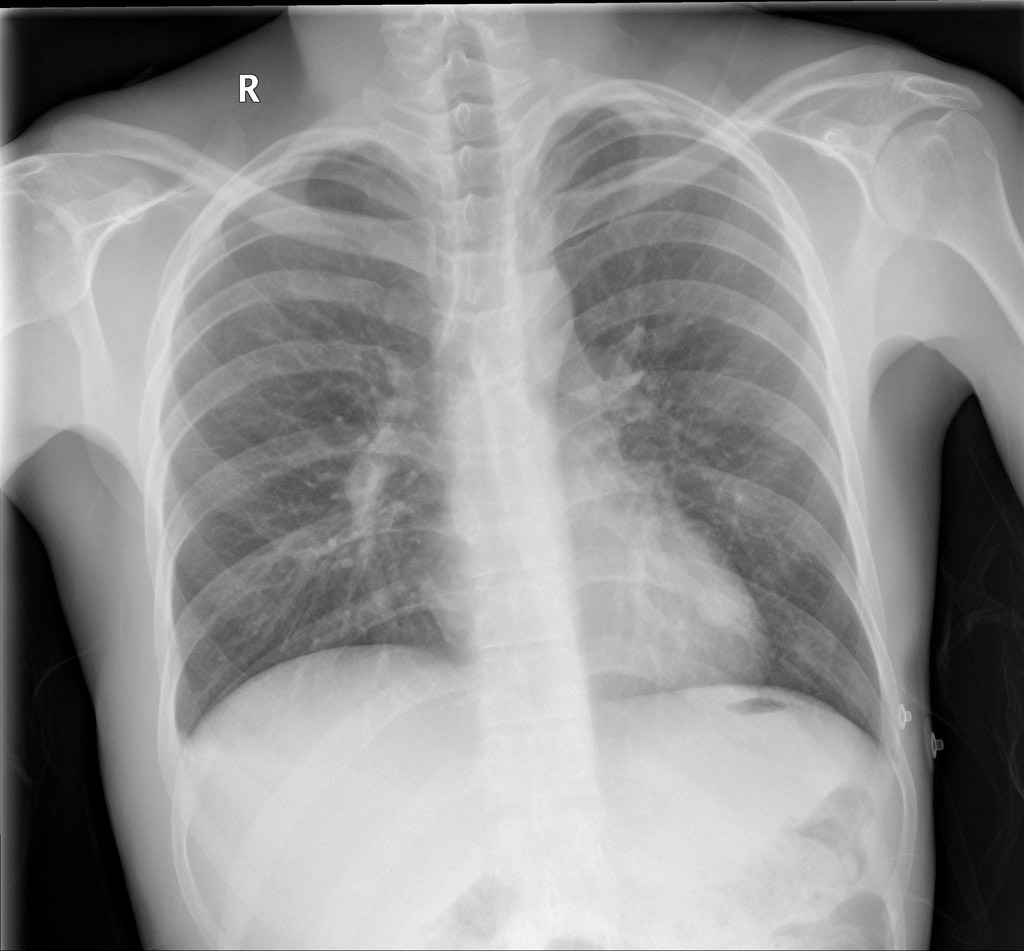

1363. Учитывая представленные на рентгенограмме данные и локализацию первичного плоскоклеточного рака в лёгком у пациента, страдающего ХОБЛ (индекс тиффно 65%), целесообразно выполнение _____________ с удалением регионарных лимфоузлов